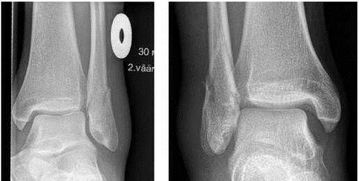

你的骨折情況看你說(shuō)不像很嚴(yán)重,你自己看的還是醫(yī)生看的?如果確定還有裂痕,那你現(xiàn)在的情況挺尷尬的。

一般來(lái)說(shuō)固定三周了,骨折線應(yīng)該已經(jīng)模糊了。但你這種只是有點(diǎn)遲緩愈合,也是正??赡艿那闆r。

首先,腳踝骨折了一定要注意到骨外科拍片做個(gè)詳細(xì)的檢查,在局部的地方進(jìn)行復(fù)位固定,在此期間切記不要隨意亂動(dòng),讓骨折位置能夠快速?gòu)?fù)原,避免移位那就麻煩。